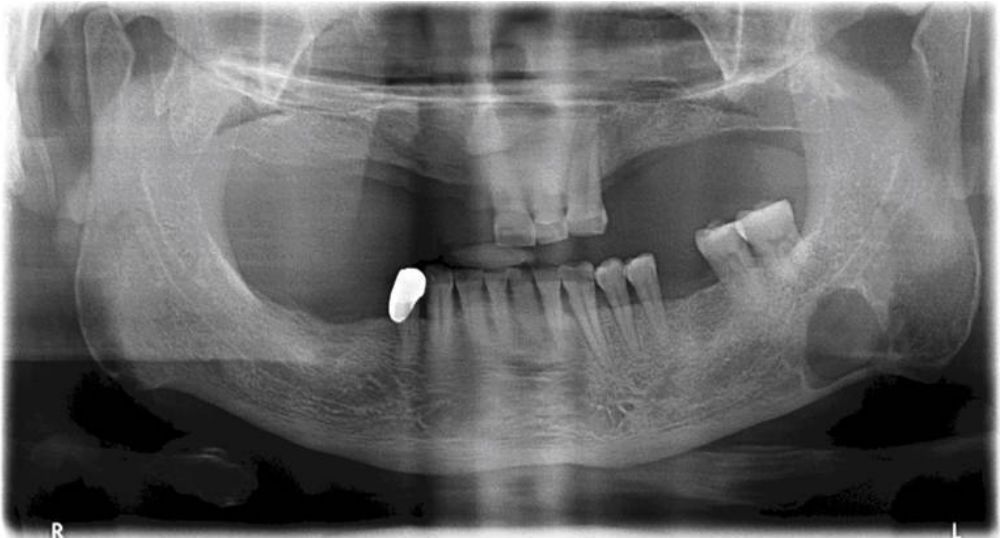

79.圖示影像是以何種方法拍攝? (A)magnetic resonance imaging (B)occlusal radiography (C)panoramic radiography (D)computed tomography